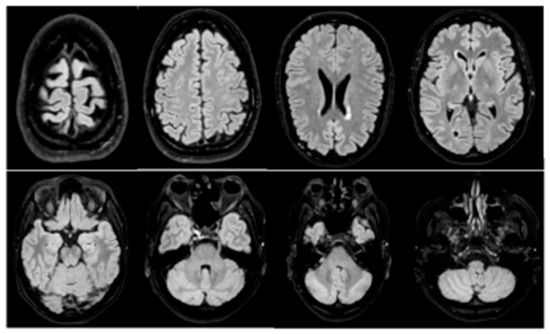

8 pages, 7998 KB

Case Report

Leptomeningeal Carcinomatosis of a Poorly Differentiated Cervical Carcinoma Caused by Human Papillomavirus Type 18

by Pierpaolo Zorzato, Mattia Zambon, Silvia Gori, Helena Frayle, Maria Teresa Gervasi and Annarosa Del Mistro

Viruses 2021, 13(2), 307; https://doi.org/10.3390/v13020307 - 16 Feb 2021

Cited by 4 | Viewed by 3682

Abstract

Cervical cancer is caused by a persistent infection with high-risk types of Papillomaviruses (hrHPV); HPV16 and HPV18 are associated with about 70% of the cases. In the last decades the introduction of a cervical cancer screening has allowed a decrease in cervical cancer [...] Read more.

Cervical cancer is caused by a persistent infection with high-risk types of Papillomaviruses (hrHPV); HPV16 and HPV18 are associated with about 70% of the cases. In the last decades the introduction of a cervical cancer screening has allowed a decrease in cervical cancer incidence and mortality; regular adhesion to the screening procedures, by pap test or HPV test, and colposcopy, according to the international guidelines, prevents cancer development and allows for diagnosis at the early stages. Nowadays, in industrialized countries, it is not common to diagnose this pathology in advanced stages, and this occurrence is frequently associated with patient’s unattendance of cervical screening programs. We describe a case of delayed diagnosis of cervical cancer, posed only after the onset of the neurological symptoms caused by leptomeningeal metastases, despite a two-year history of abnormal cytology. The endocervical mass was analyzed by immunohistochemistry, and search and typing of HPV sequences was performed by PCR in the meningeal carcinomatous cells. A poorly differentiated squamous cell carcinoma was diagnosed, and HPV18 sequences were detected. This rapidly fatal case highlights the importance of following the evidence-based recommended protocols and the preventive role of the population-based cervical cancer screening programs. Full article

(This article belongs to the Special Issue HPV and HPV Vaccine)

Show Figures

Figure 1